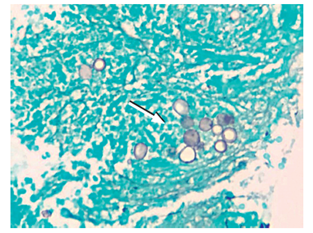

No hubo complicaciones relacionadas con el procedimiento (Figura 2). El reporte de histopatología fue la presencia de necrosis e inflamación, y a la coloración de Gomori-Grocott se evidenció la presencia de levaduras multigemantes de tamaño variable compatibles con paracoccidioidomicosis. La tinción de Ziehl-Neelsen fue negativa para bacilos ácido-alcohol resistentes y no se evidenció malignidad en la muestra (Figuras 3 y 4). El paciente recibió manejo con anfotericina B hasta completar el esquema y fue dado de alta por mejoría clínica evidente, con manejo ambulatorio con itraconazol y prednisona oral.

El diagnóstico definitivo se realiza con la visualización microscópica de células gigantes tipo Langhans y levaduras con gemación múltiple en patrón de timón de barco, con una mayor que tiene varias menores en gemación, en su periferia. Las tinciones del ácido peryódico de Schiff (PAS) y de plata permiten una mejor visualización de dicho hallazgo 6.